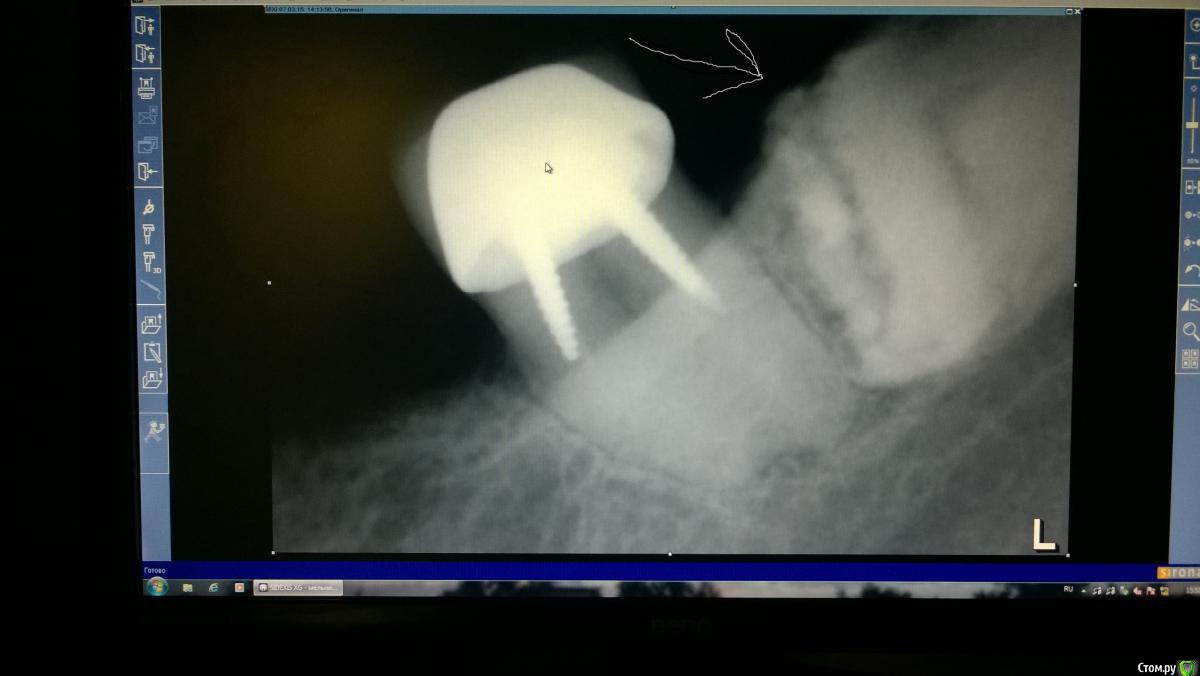

krokomot Опубликовано 8 марта, 2015 Поделиться Опубликовано 8 марта, 2015 Предлагаю оценить снимок и высказать предположения по поводу объекта указанного стрелкой. Задание не сложное для развлекухи не судите строго)) Ссылка на комментарий

Romanson Опубликовано 15 марта, 2015 Поделиться Опубликовано 15 марта, 2015 что значит перевернутая?http://i.piccy.info/i9/7bd24d612a28975971e10e49c394021b/1426403447/87618/868061/fs_1.jpgКрасным обведены контуры зуба, зеленым контуры пульпы. Не?) Ссылка на комментарий

krokomot Опубликовано 15 марта, 2015 Автор Поделиться Опубликовано 15 марта, 2015 http://i.piccy.info/i9/7bd24d612a28975971e10e49c394021b/1426403447/87618/868061/fs_1.jpgКрасным обведены контуры зуба, зеленым контуры пульпы. Не?)Правильно! Это ретенированный зуб 3.8, у бабули 80 лет, проризошла его 50% структурная резорбция. зуб стал практически частью кости Ссылка на комментарий

Romanson Опубликовано 15 марта, 2015 Поделиться Опубликовано 15 марта, 2015 Правильно! Это ретенированный зуб 3.8, у бабули 80 лет, проризошла его 50% структурная резорбция. зуб стал практически частью костиНу такая себе загадка) АнтонТЛТ сразу "отгадал" Он её беспокоил как-то? Расскажите как удаляли? 1 Ссылка на комментарий

krokomot Опубликовано 15 марта, 2015 Автор Поделиться Опубликовано 15 марта, 2015 Ну такая себе загадка) АнтонТЛТ сразу "отгадал" Он её беспокоил как-то? Расскажите как удаляли?Нет конечно, не удалял, удаление этого зуба равносильно забору обьемного костного блока))А так интересно было услышать мнения врачей, ну и ваш ответ оказался самым определенным)) Ссылка на комментарий

krokomot Опубликовано 15 марта, 2015 Автор Поделиться Опубликовано 15 марта, 2015 По снимку конечно Ссылка на комментарий